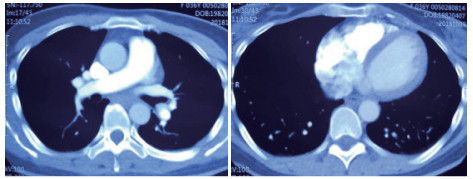

2 积极寻找补救性溶栓的治疗时机并非遥不可及例3 36岁,女性。主诉“活动后气短5 d、加重伴咯血1 d”。既往因月经不调,应用激素替代治疗20 d;否认手术、外伤及制动史。入院查体:神志清楚,体温36.8℃,血压110/75 mmHg,脉率118次/min,呼吸23次/min,脉氧饱和度90%(安静,空气氧),轻度乏氧征。双肺呼吸音清。心率118次/min,未闻及干、湿性啰音,心律齐,P2 > A2,心界无扩大,无杂音,腹软,无压痛,肠鸣音正常,双下肢无浮肿。神经系统查体未见异常。血气分析(空气氧)提示pH 7.415,PaCO2 38.3 mmHg,PaO2 89.90 mmHg,SaO2 89.90%;D-Dimer 1 684 ng/mL;FDP 8.670 μg/mL,FBG 3.510 g/L;PLT 151.0 G/L;cTnI 0.00 ng/mL,BNP 58.00 ng/mL;ALT 27 U/L,AST 17 U/L,CREA 53.7 μmol/L,血Na+、K+、Cl-大致正常;UCG提示:右室壁运动减低,左室壁运动不协调,各室壁厚度正常,三尖瓣环位移14 mm,右室面积变化率19%,各瓣膜形态及运动未见异常,收缩期三尖瓣房侧见少量反流信号,T1法估测SPAP:24 mmHg;双下肢静脉超声提示:右下肢深静脉血栓形成。心电图(图 8所示)提示窦性心动过速;CTPA提示双肺主干明确充盈缺损(图 9所示)。入院诊断:急性PE(中低危)。给予低分子肝素抗凝治疗。入院24 h内,大便时出现胸闷、心悸主诉,SpO2由93%(不吸氧)降至88%(储氧面罩吸氧,Flow 10 L/min);D-Dimer由入院时1 026 ng/mL升至4 100 ng/mL,血压110/70 mmHg。因血氧有恶化趋势遂决定给予静脉溶栓治疗(r-tPA 50 mg,2 h内泵入),溶栓治疗结束后2 h复查凝血提示D-Dimer 45 000 ng/mL。溶栓2 h患者症状明显好转;心电图提示窦性心动过速,SⅠQⅢTⅢ征象较前改善,胸前导联出现冠状T波(图 10所示)。溶栓后24 h复查CTPA右肺主干血栓明显消失,右心室较前明显缩小(图 11所示)。

| 图 9 入院时CTPA提示右肺动脉主干充盈缺损、左肺亚段水平充盈缺损、右心室增长 |

| 图 11 溶栓后CTPA提示原有血栓完全溶解、右心室较前明显缩小 |